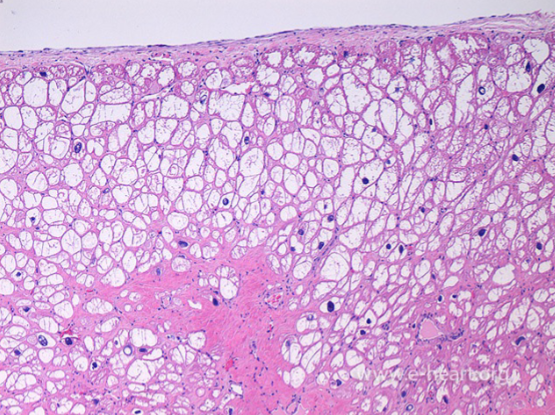

This tissue has changed due to injury. Why type of change has occurred

Hydropic change (Accumulation of water in the cytoplasm)

This Liver tissue has changed due to injury. Why type of change has occurred